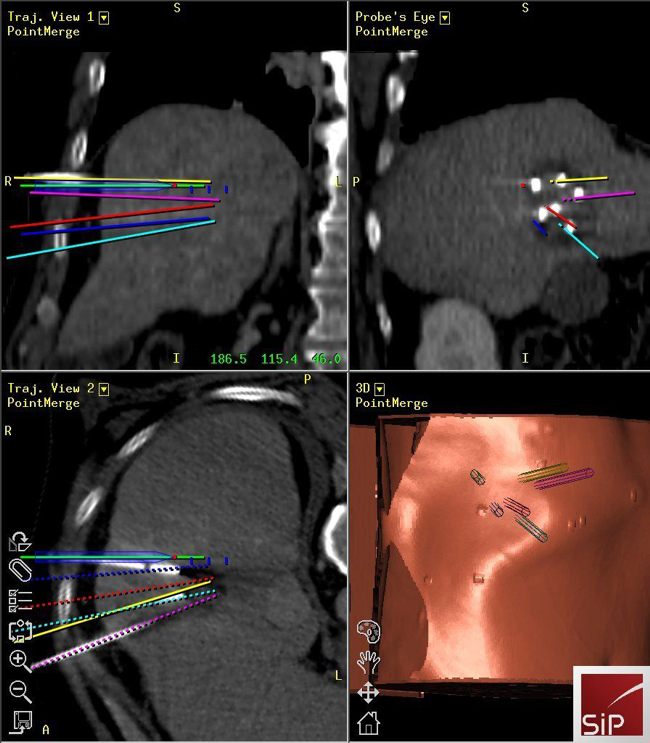

Interventional Oncology

Reto Bale

Stereotactic ablation of liver tumours:

Radiofrequency ablation (RFA) allows local curative tumour treatment by inducing coagulation necrosis with a high-frequency alternating current. The major limiting factor of conventional US- and CT- guided percutaneous single probe ablation is the tumour size. Navigation systems allow for 3D-planning of multiple overlapping ablation zones on the CT datasets and precise transformation into the real patient. We developed the worldwide first aiming device for frameless stereotactic punctures and performed the first in man stereotactic radiofrequency ablation (SRFA) of a liver tumor in 2001. Meanwhile > 1000 patients with > 3000 liver tumors, most of them being inoperable, have successfully been treated at our department.